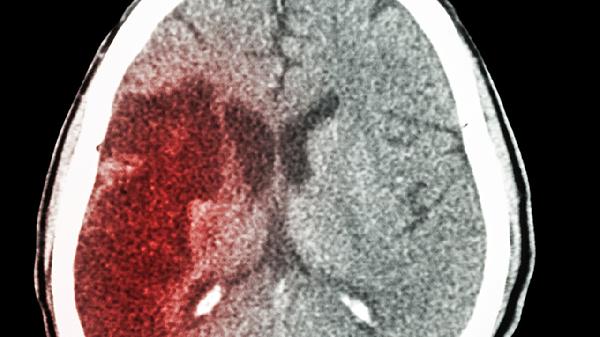

安宫牛黄丸是一种传统中成药,主要成分包括牛黄、麝香、冰片等,具有清热解毒、开窍醒神的功效。在脑梗急性期,部分患者可能出现高热、神志不清等症状,此时安宫牛黄丸可能通过其清热开窍的作用缓解症状。但需注意,脑梗的核心治疗是尽快恢复血流,如静脉溶栓或血管内取栓,安宫牛黄丸仅作为辅助手段,不能延误关键治疗时机。